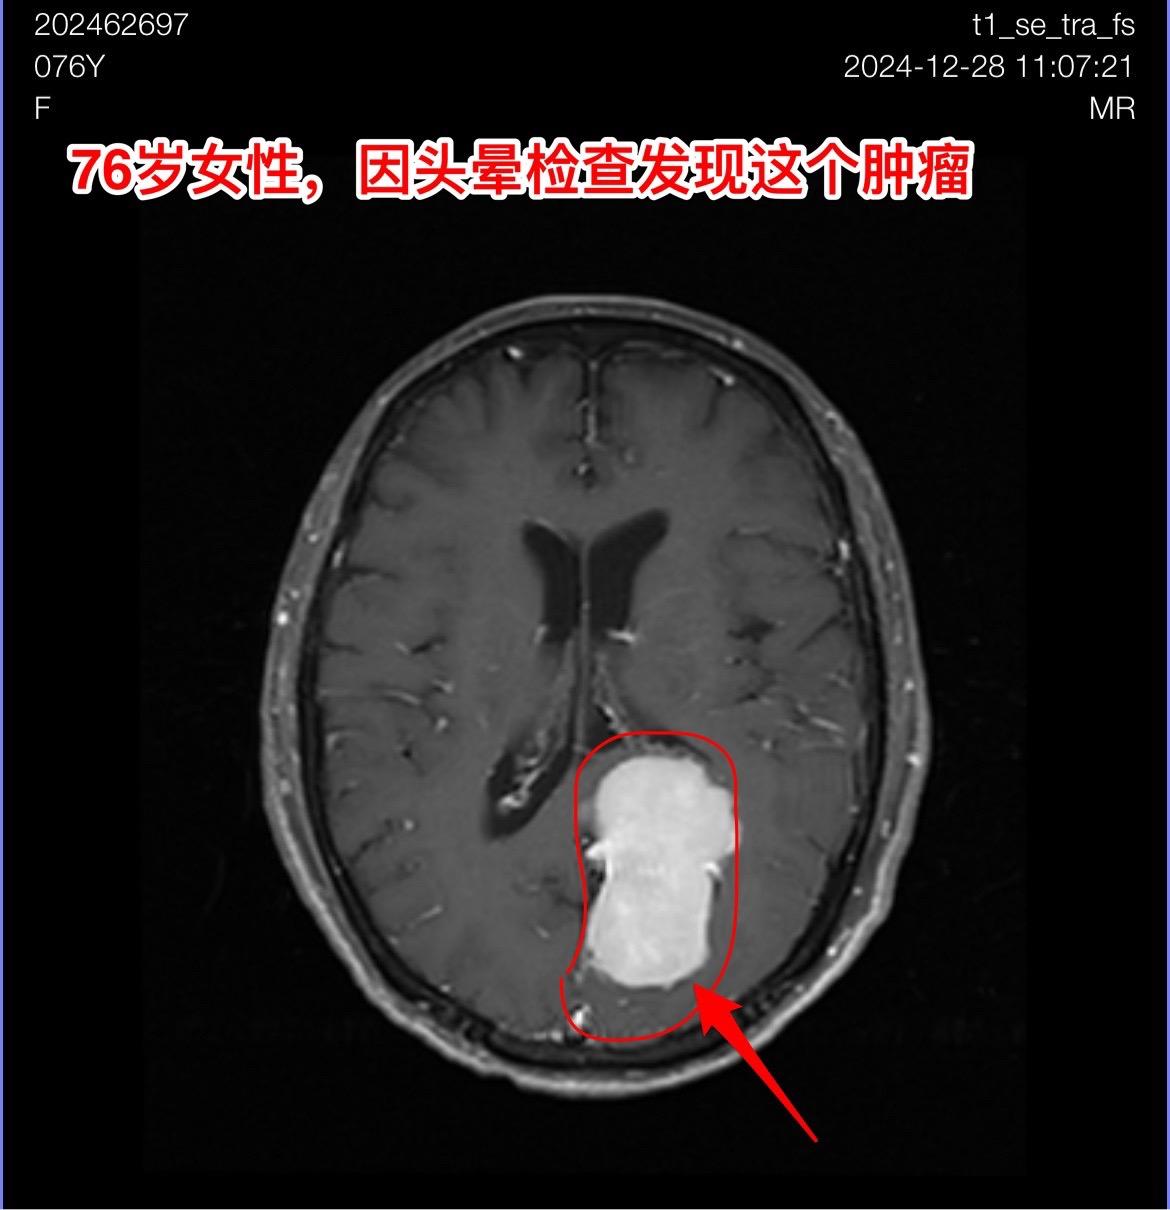

76岁女性,发现脑肿瘤需要作手术吗?山东省菏泽市的76岁女性,因头晕症状到医院去 头部磁共振检查,结果发现脑部长了一个大肿瘤,见图。 家人急切地想知道:是不是要立即动手术? 病人两年前还作过乳腺癌手术和甲状腺肿瘤切除手术。还有糖尿病病史20年。体重只有八十来斤。 这个老人需要立即作手术吗? 我看磁共振照片后印象是脑膜瘤。鉴于病人的身体状况不好,高龄,症状也不重,我建议先观察一段时间,不急于作手术。 朋友们,你们的意见是什么?